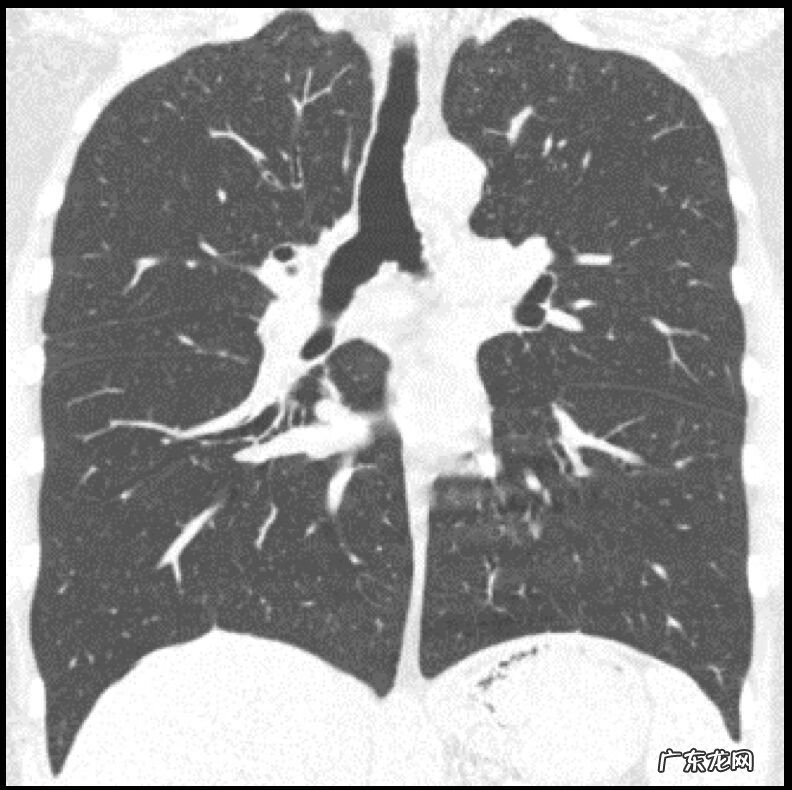

VS ANCA相关血管炎

ANCA相关血管炎也能看到反晕征,沿支气管血管束分布,病变周围也是结节状的改变,也有可能是ANCA相关血管炎 。但是ANCA相关血管炎的临床表现有哮喘或过敏性鼻炎或嗜酸性粒细胞增高,除了反晕征以外,双肺磨玻璃影或实变影一般呈对称性分布,支气管壁增厚并支气管扩张不多见,周边胸膜下显著,反晕征为肺出血和边缘机化性肺炎形成 。

这是一位嗜酸性肉芽肿性多血管炎(EGPA)的患者,咳喘 1年余,逐渐加重,有过敏性鼻炎/鼻窦炎14年的病史 。患者出现典型的全身症状,外周血白细胞↑,嗜酸性粒细胞百分比31.2% ↑,心肌酶升高,胃肠道症状,皮疹,血沉加快,CRP增高,ANCA (-) PR3(-) MPO(-),气管粘膜活检:基底膜及间质见嗜酸性粒细胞浸润 。治疗3个月后肺内病变明显吸收(图5) 。这个病例从临床表现,就已经排除了很多疾病 。